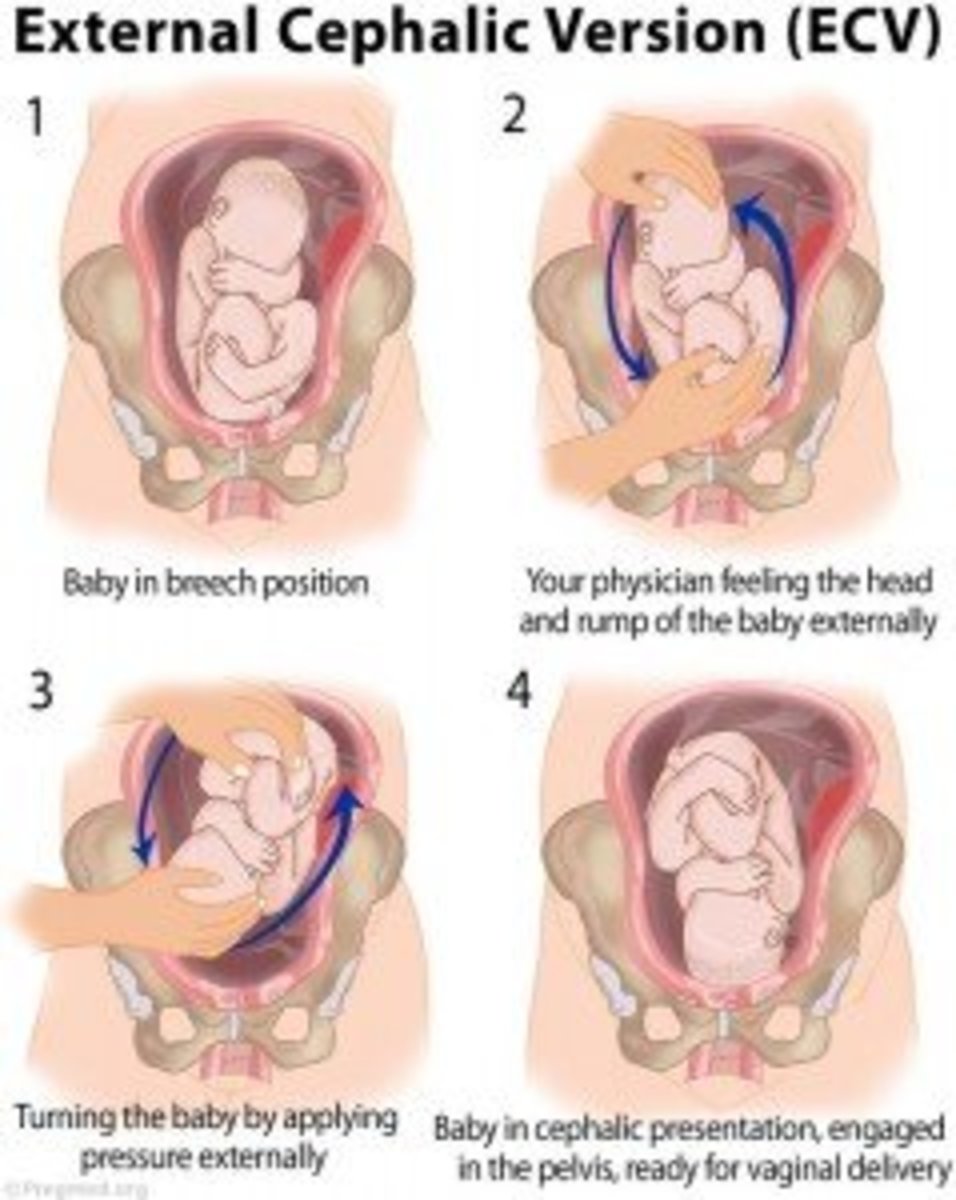

External Cephalic Version(ECV) technique for Breech Baby